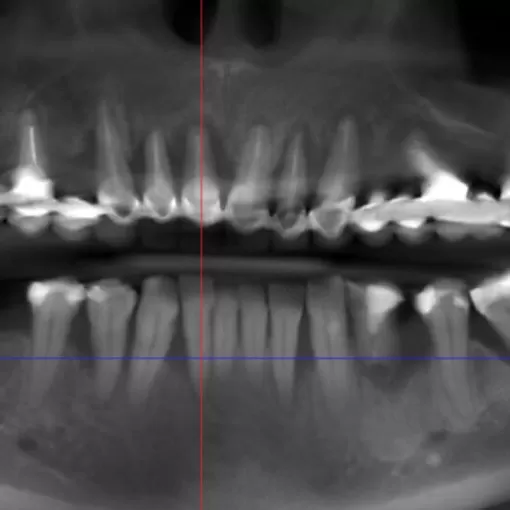

Пациент обратился с целью имплантации в области отсутствующего зуба 4.6. Однако после КЛКТ (3Д) исследования был обнаружен воспалительный процесс (киста) в области соседнего зуба 4.7 (рис. 1).